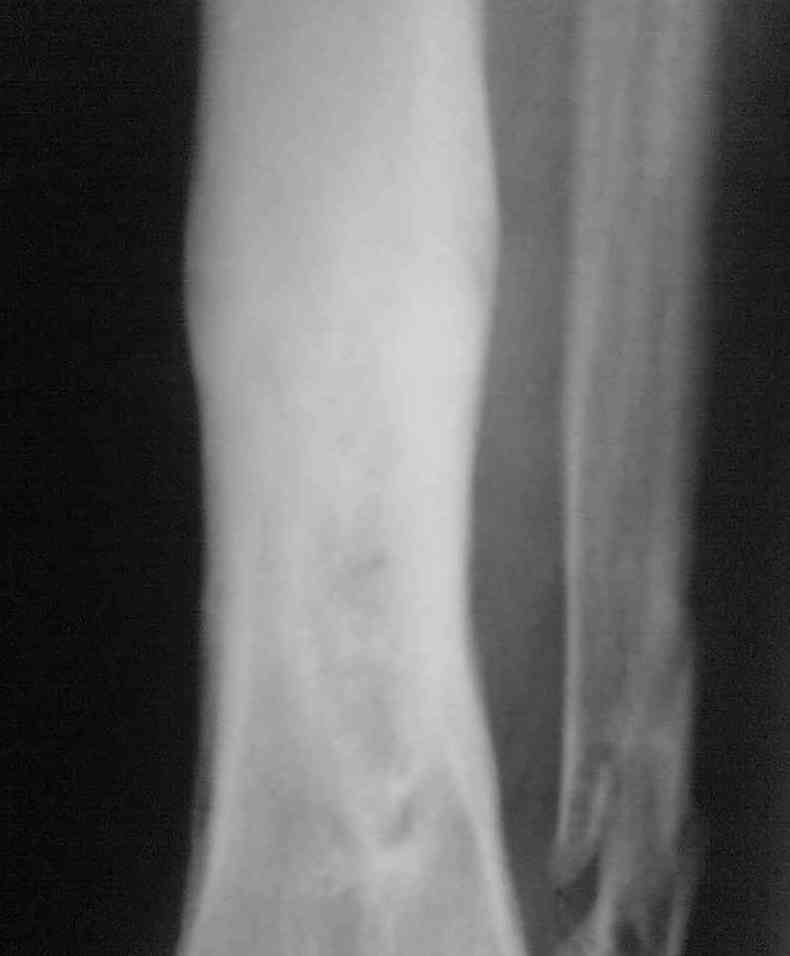

Re: Остеомиелит.

Выкладываю снимки в хронологическом порядке. Снмки все какие есть у больного.